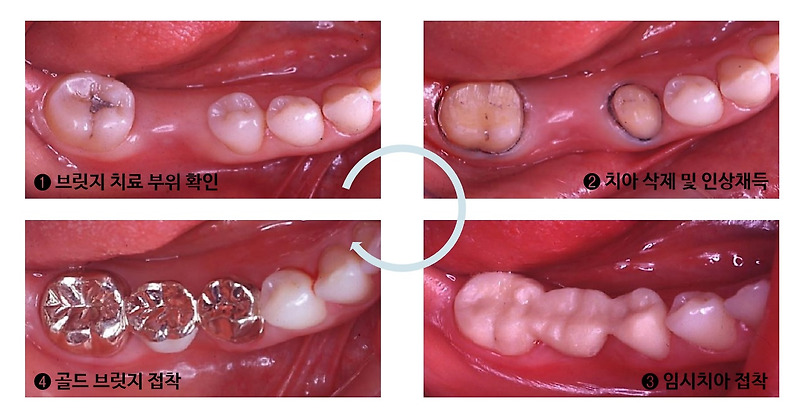

안녕하세요 의정부바른성치과입니다오늘은 보철치료인 <브리지>에 대해 알아보겠습니다.여러분 한번쯤 들어보셨을텐데 이해하기 쉽게 설명해드릴게요!위 그림과 같이 가운데 치아가 빠졌을 때 양쪽 치아를 깎아 발처럼 걸어 사용하는 보철치료입니다.가운데 치아가 빠지면 가운데 치아만 임플란트를 하면 되는데 왜 브릿지 치료가 필요할까요?간혹 임플란트 치료가 불가능하거나 힘든 경우가 있습니다.대표적인 예로 임플란트를 식립할 뼈가 턱없이 부족한 경우 골다공증 약을 오래 복용하고 수술 시 골괴사 위험이 있는 경우, 당뇨병이 매우 심하여 수술 시 회복력이 떨어지는 경우 등이 있는데, 이 경우 임플란트 치료 대신 브릿지 치료를 시행합니다.저희 병원에서 실시한 간단한 브릿지 치료 케이스를 소개해 드리도록 하겠습니다.한참 전에 어금니 하나가 빠진 환자예요.치아가 상실된 지 오래되었기 때문에 앞니가 이동하게 되었고, 뒷니도 신경치료가 필요하여 모두 함께 치료를 진행하기 위해 브릿지로 나아가게 되었습니다.한참 전에 어금니 하나가 빠진 환자예요.치아가 상실된 지 오래되었기 때문에 앞니가 이동하게 되었고, 뒷니도 신경치료가 필요하여 모두 함께 치료를 진행하기 위해 브릿지로 나아가게 되었습니다.앞뒤 치아 모두 신경 치료를 먼저 하고 브릿지 치료를 실시했습니다.앞뒤 치아 모두 신경 치료를 먼저 하고 브릿지 치료를 실시했습니다.앞뒤 치아 모두 신경 치료를 먼저 하고 브릿지 치료를 실시했습니다.치료전 치료후 치료완료후 엑스레이 사진입니다 치료전 치아사이의 공간과 상실된 치아부분은 브릿지치료를 통해 모두 해결되었습니다치료전 치료후 치료완료후 엑스레이 사진입니다 치료전 치아사이의 공간과 상실된 치아부분은 브릿지치료를 통해 모두 해결되었습니다치료전 치료후 치료완료후 엑스레이 사진입니다 치료전 치아사이의 공간과 상실된 치아부분은 브릿지치료를 통해 모두 해결되었습니다브릿지 완료 후 구강 내 모습입니다 육안으로 봐도 치간의 공간이나 상실부위가 없어지고 가운데 비어있던 공간에 치아가 생기고 저작기능도 회복되었습니다^^이상 <브리지> 치료에 대해 알아봤습니다.치아가 빠진 채로 있거나 임플란트가 불가능하다는 진단을 받으신 분은 <바른손치과>에 내원하셔서 검진을 받아보시기 바랍니다. ^^바른손치과의원 경기도 의정부시 동일로 46 82층#의정부바른손치과 #신곡동바른손치과 #의정부치과추천 #의정부 임플란트 #의정부 틀니 #의정부보험 임플란트 #의정부보험 틀니 #의정부치과보철 #의정부신경치료 #의정부브릿지 #의정부크라운 #의정부레진 #의정부치과충치치료 #의정부치아미백 #의정부사랑니 #의정부악관절 # 의정부스케일링 # 의정부안아픈치아 #노원치과추천 #포천치과추천 #양주 임플란트